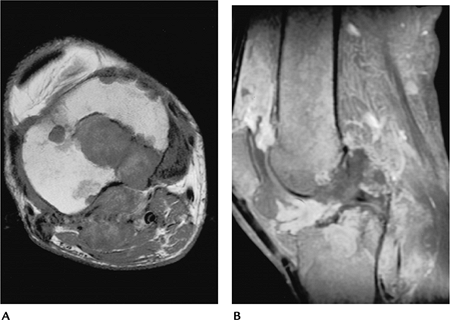

![]() |

|

FIGURE 13-37 PVNS. Sagittal T1- (A) and T2- (B)